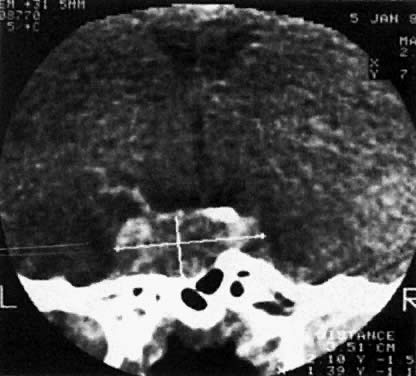

Both CT and MRI scans are adequate for the diagnosis of both microadenomas and macroadenomas (Fig. 2 and Fig. 3). Both of these radiographic techniques can detect a pituitary tumor as small as 2 mm. There is considerable difference in the cost of a CT and MRI scan ($758 versus $1,490, respectively). MRI scanning is advantageous if longitudinal surveillance is necessary over a lifetime because no radiation exposure is incurred with this technique.

Fig. 2. CT scan of a patient with suprasellar macroadenoma.